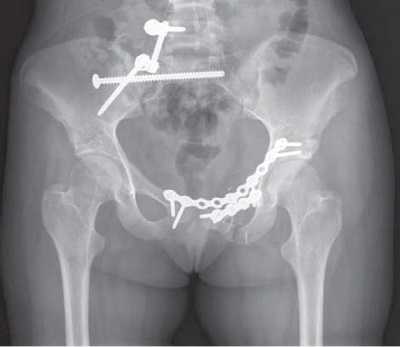

Открытая репозиция и внутренняя фиксация. В ходе операции костные фрагменты в первую очередь возвращаются в нормальное анатомическое положение (репонируются). Для удержания фрагментов в этом положении до наступления сращения используются металлические пластины и винты.

В данном случае для стабилизации перелома костей таза использованы пластины и винты. Осложнения